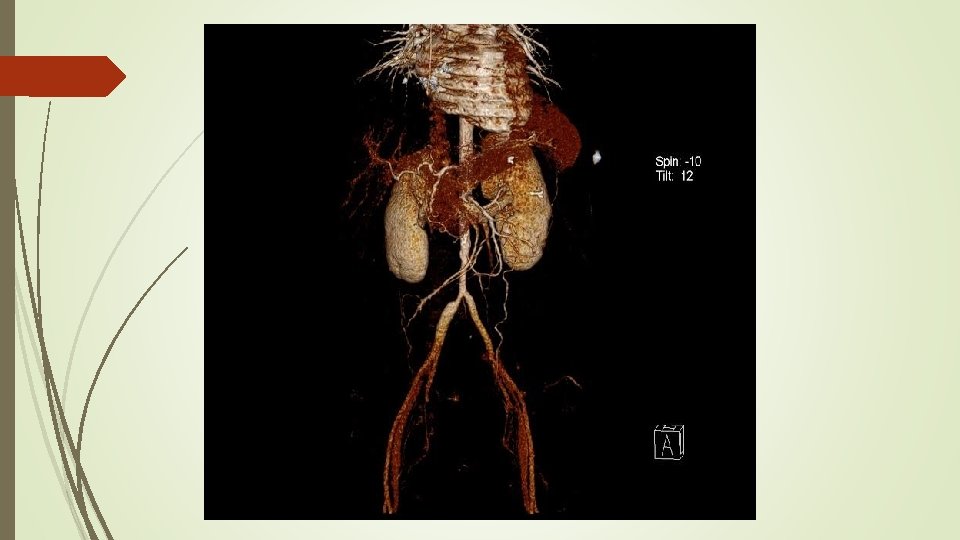

Angio. TAC aorta helicoidal sincronizado - Engrosamiento en forma de semiluna de aorta torácica ascendente y un engrosamiento circunferencial difuso de arco aórtico y aorta torácica descendente, alcanzando la bifurcación ilíaca. - Engrosamiento circunferencial del origen los troncos supraaórticos con estenosis filiforme del origen y primeros centímetros de carótida común izquierda. - Oclusión de arteria subclavia izquierda desde origen de arteria vertebral con repermeabilización de arteria axilar por colaterales. - Estenosis de la aorta abdominal en todo su recorrido siendo filiforme a nivel infrarrenal con diámetro mínimo de 5 mm. - Dilatación post estenótica ilíaca de común derecha. Hallazgos compatibles con Enfermedad Takayasu en fase crónica